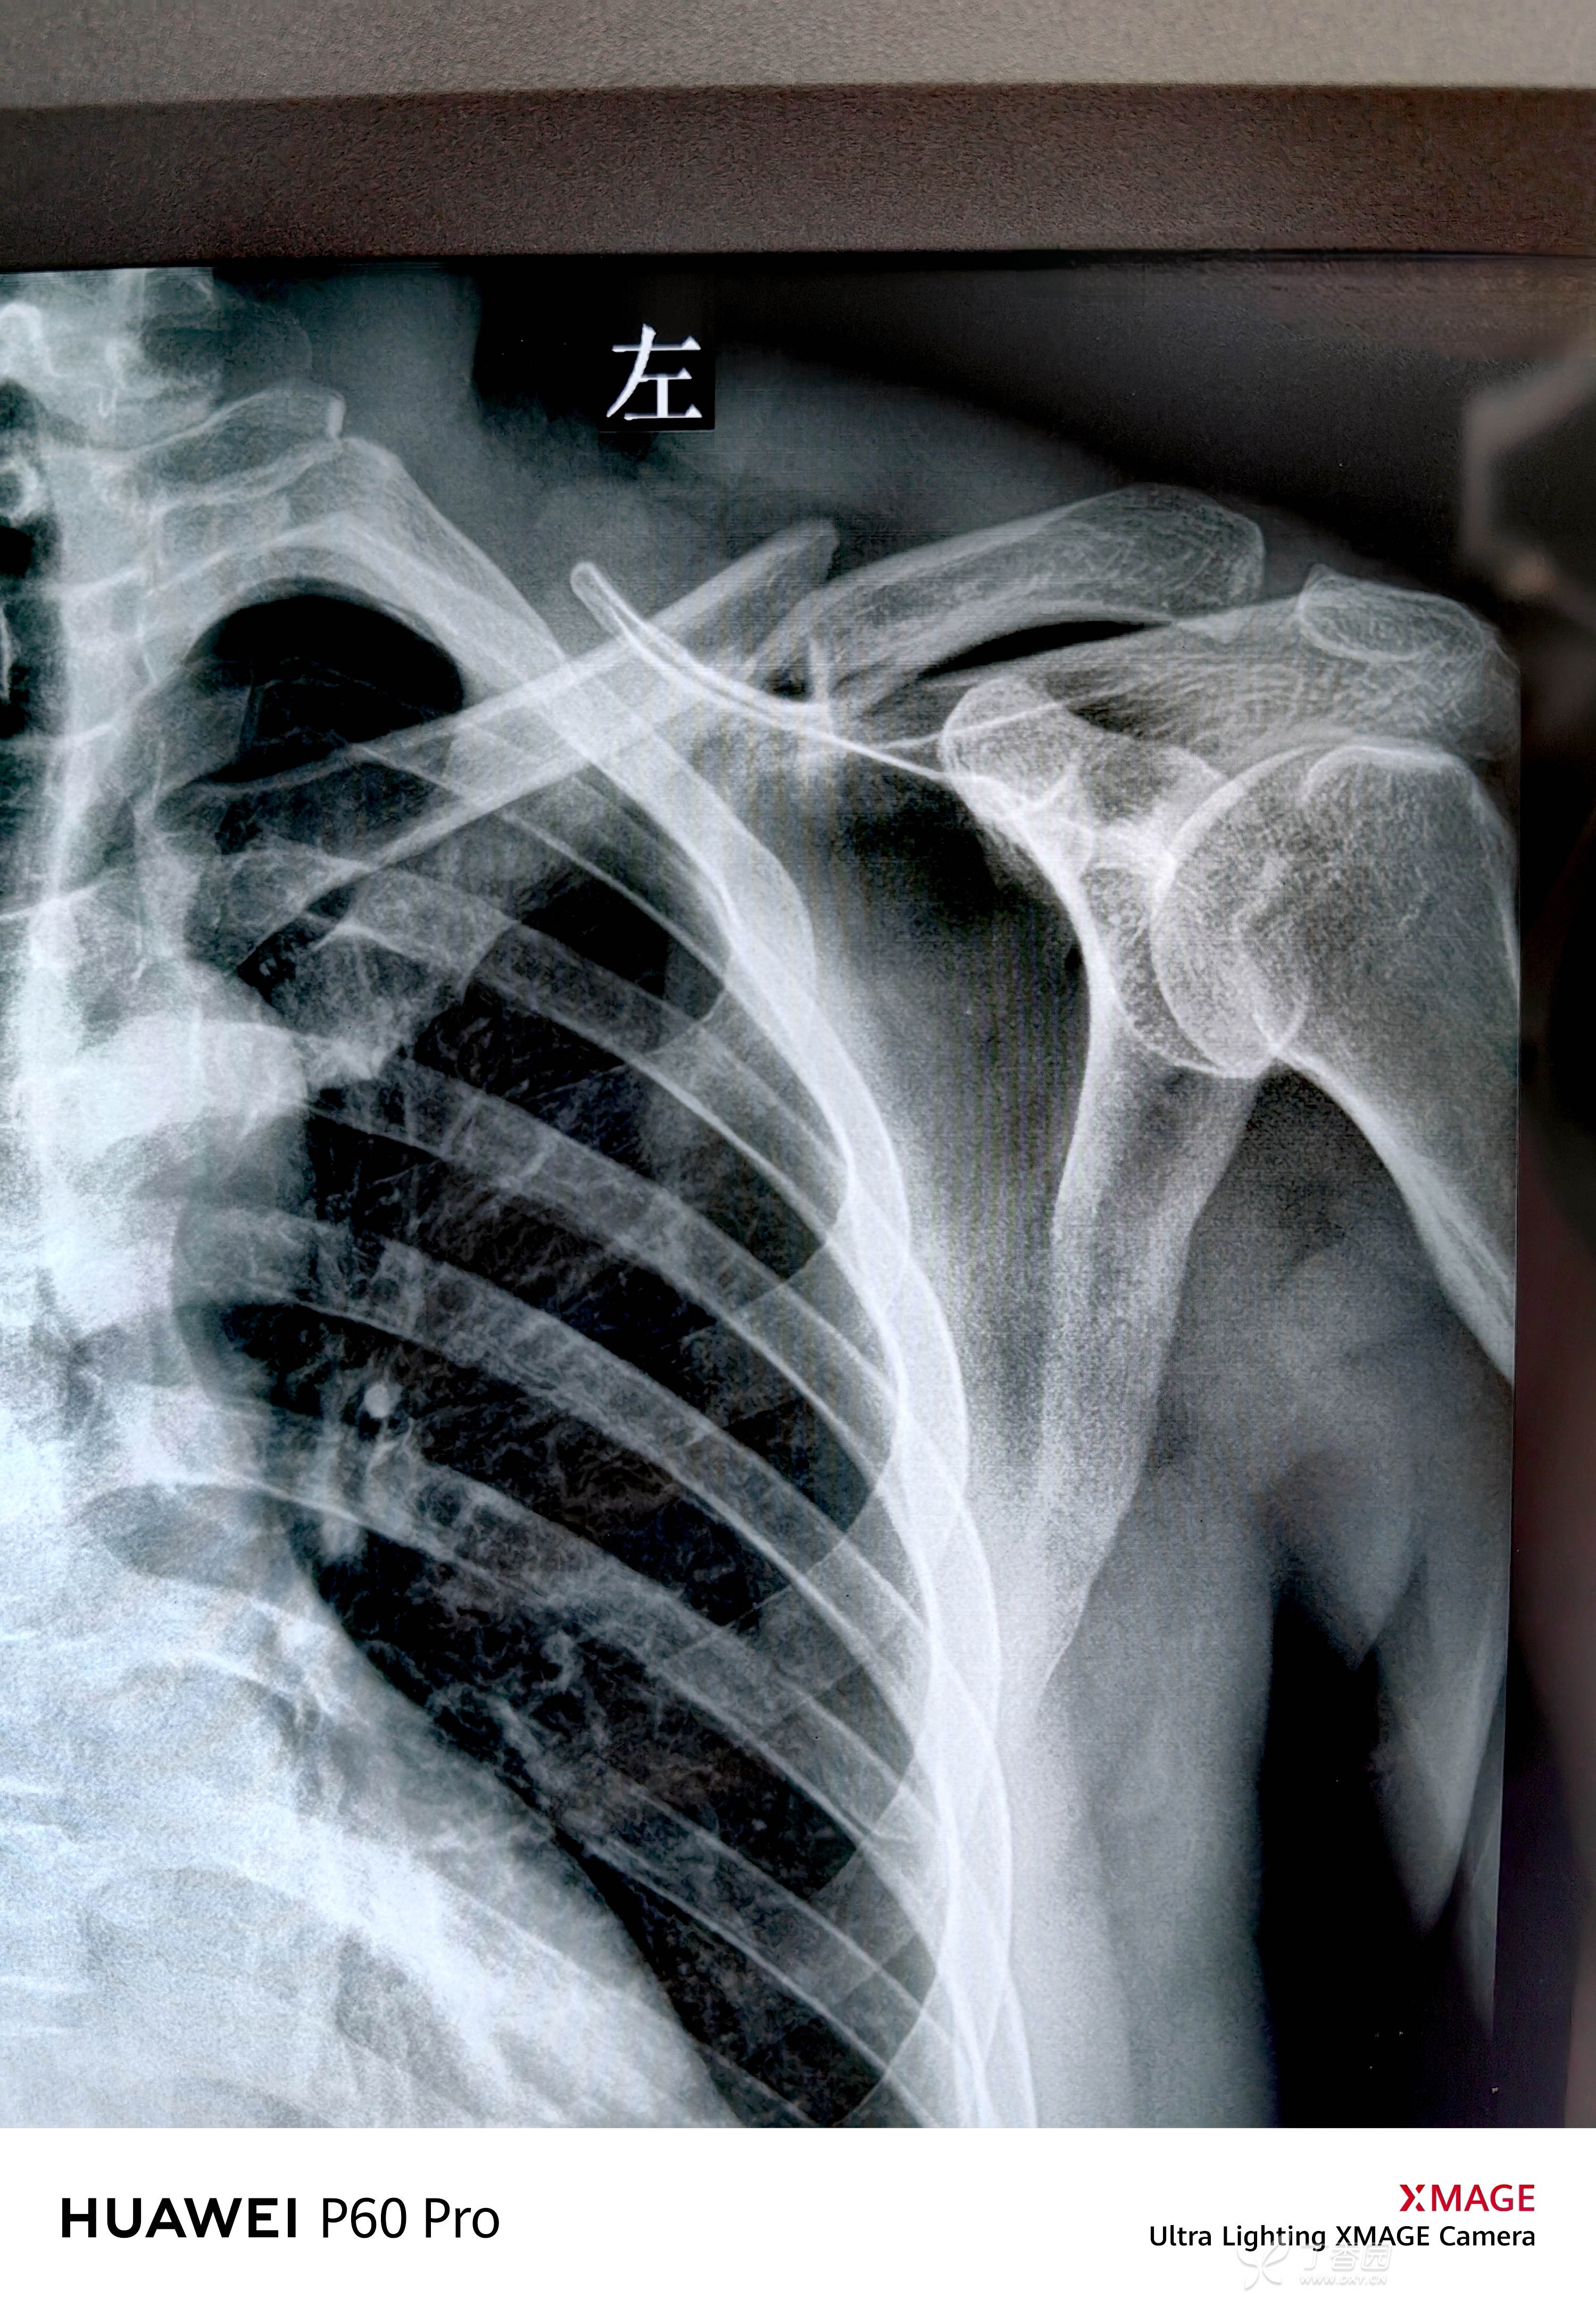

主诉:摔伤致左肩部疼痛、活动受限1天。

简要病史:患者1天前自家盖房子时不慎踩空从楼梯翻滚摔伤,当即左肩部疼痛,活动受限,就诊于当地医院,其告知3天后手术,患者为求急诊手术,随来我院,门诊检查后急诊手术,

辅助检查:

外观:可见橘皮征,骨折端卡压软组织